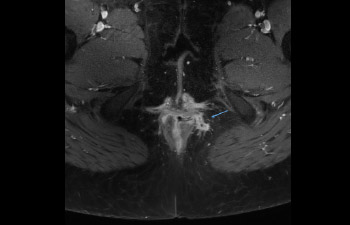

Find the right clinical applications for your needs